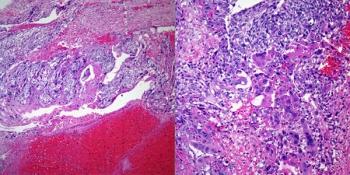

A 53-year-old woman presented with pain in the abdomen. Physical examination and radiographic imaging shows the presence of an abdominal mass. Biopsy of the mass was performed. What is your diagnosis?